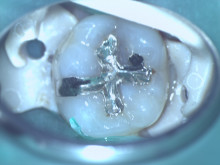

| 根の治療 |

ラバーダム防湿、マイクロスコープ使用

※そのほか金属の除去やファイバーコア等で別途費用が掛かる場合があります。 |

30,000円〜 |